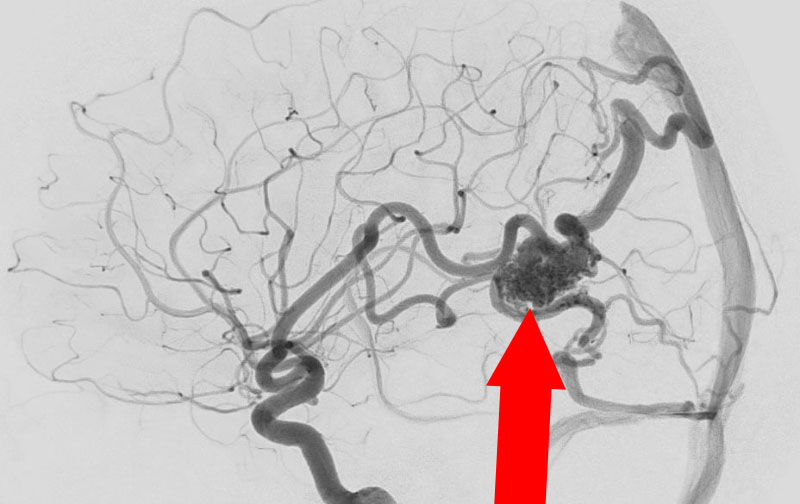

'24年8月

左前頭葉脳動静脈奇形

10代

秋田県の病院

No.1494 手術前